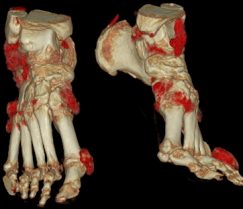

智能化、丰富的图像后处理软件

天河640层CT搭配前沿的AI人工智能技术,一键提取血管,观察病变立体直观。痛风石能谱成像、泌尿系结石成份分析助力临床治疗方案选择。

图片说明:肝脏病变3D成像、痛风石能谱成像